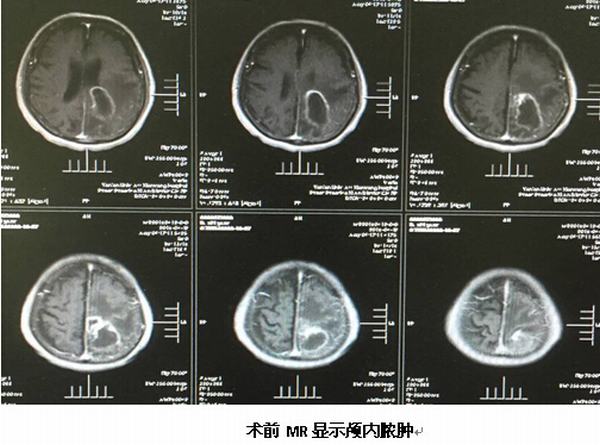

2016年4月21日凌晨2点,闫女士突然出现头痛、左侧肢体无力等症状,当晚即被家人紧急送医,经查,她大脑的右侧颞叶出现脑出血。经过细致的准备,我院神经外科医护人员为闫女士实施了脑立体定向手术,术前安装头架,头颅CT扫描,设定靶点并计算坐标,术中安装弓形架等,将引流管精确植入靶点---血肿正中心,顺利抽出血肿,术后CT验证立体定向手术精确。现经治疗10多天后患者已独立下床活动,恢复理想。

继完成第一例脑立体定向手术后不久,于2016年4月25日我院神经外科又完成一例89岁高龄脑脓肿患者的脑立体定向脓肿穿刺引流术,按照手术标准流程操作,术中清除脓液约30ml,经置管持续引流并局部及全身注射抗菌素治疗,目前患者头颅CT显示脓腔已消失,体温正常,神志清楚,各项生命体征平稳。